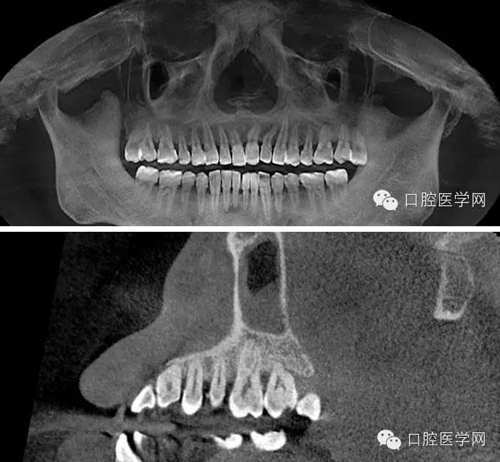

處置:必蘭局部麻醉后,于有出血點(diǎn)的牙齦乳頭處行縫合術(shù),縫合后出血明顯減少,組織同事會診,同樣口內(nèi)無明顯臨床表現(xiàn),拍攝CBCT,CT顯示26根尖可見低密度透射暗影,35、36、37無異常,為進(jìn)一步確診,遂與患者溝通采用麻醉排除法確認(rèn)患牙。26必蘭麻頰腭側(cè)浸潤麻醉,待麻藥起效后,患者告知牙齒疼痛停止,觀察五分鐘無其他異常,遂確認(rèn)患牙,建議患者行根管治療術(shù)。交代治療過程,治療風(fēng)險(xiǎn),簽署治療同意書。

CBCT截圖:26根尖可見低密度透射暗影: